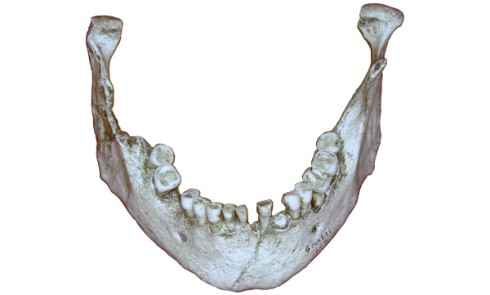

Examen clinique Le jeune Yoan 9 ans est adressé par son chirurgien maxillofacial, suite à l’exérèse d’un kyste bénin du...